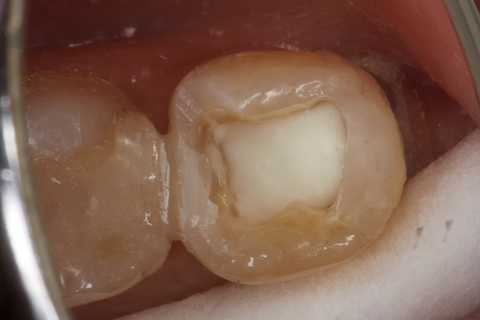

この症例は歯根内部をいじられていないので、根管治療は難しくない。CRで歯冠を再建するのが難しかった。

再建が終わった後で、内部の治療をしてCRで埋め戻している。